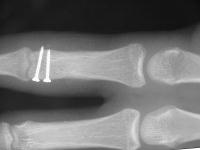

Clinical Example: Unicondylar proximal phalanx head fracture with micro screws

Unicondylar fractures of the phalangeal head are common, frequently unstable and unacceptably displaced. Although some may be treated successfully with percutaneous reduction and fixation, many require open reduction. In these cases, the screws were put right through the collateral ligament and sunk into the cortex. I think the simplest way to do this is to reduce and stabilize with two K wires, then remove the wires and replace with screws, one at a time, so reduction is maintained throughout. 1mm=39/1000" Kwire, so doing the math, here is how you choose the right sized Kwire to use as both drill and provisional fixation:

With two screws, bicortical fixation is not needed. The video below illustrates the steps involved, which are the same with either open or percutaneous fixation.